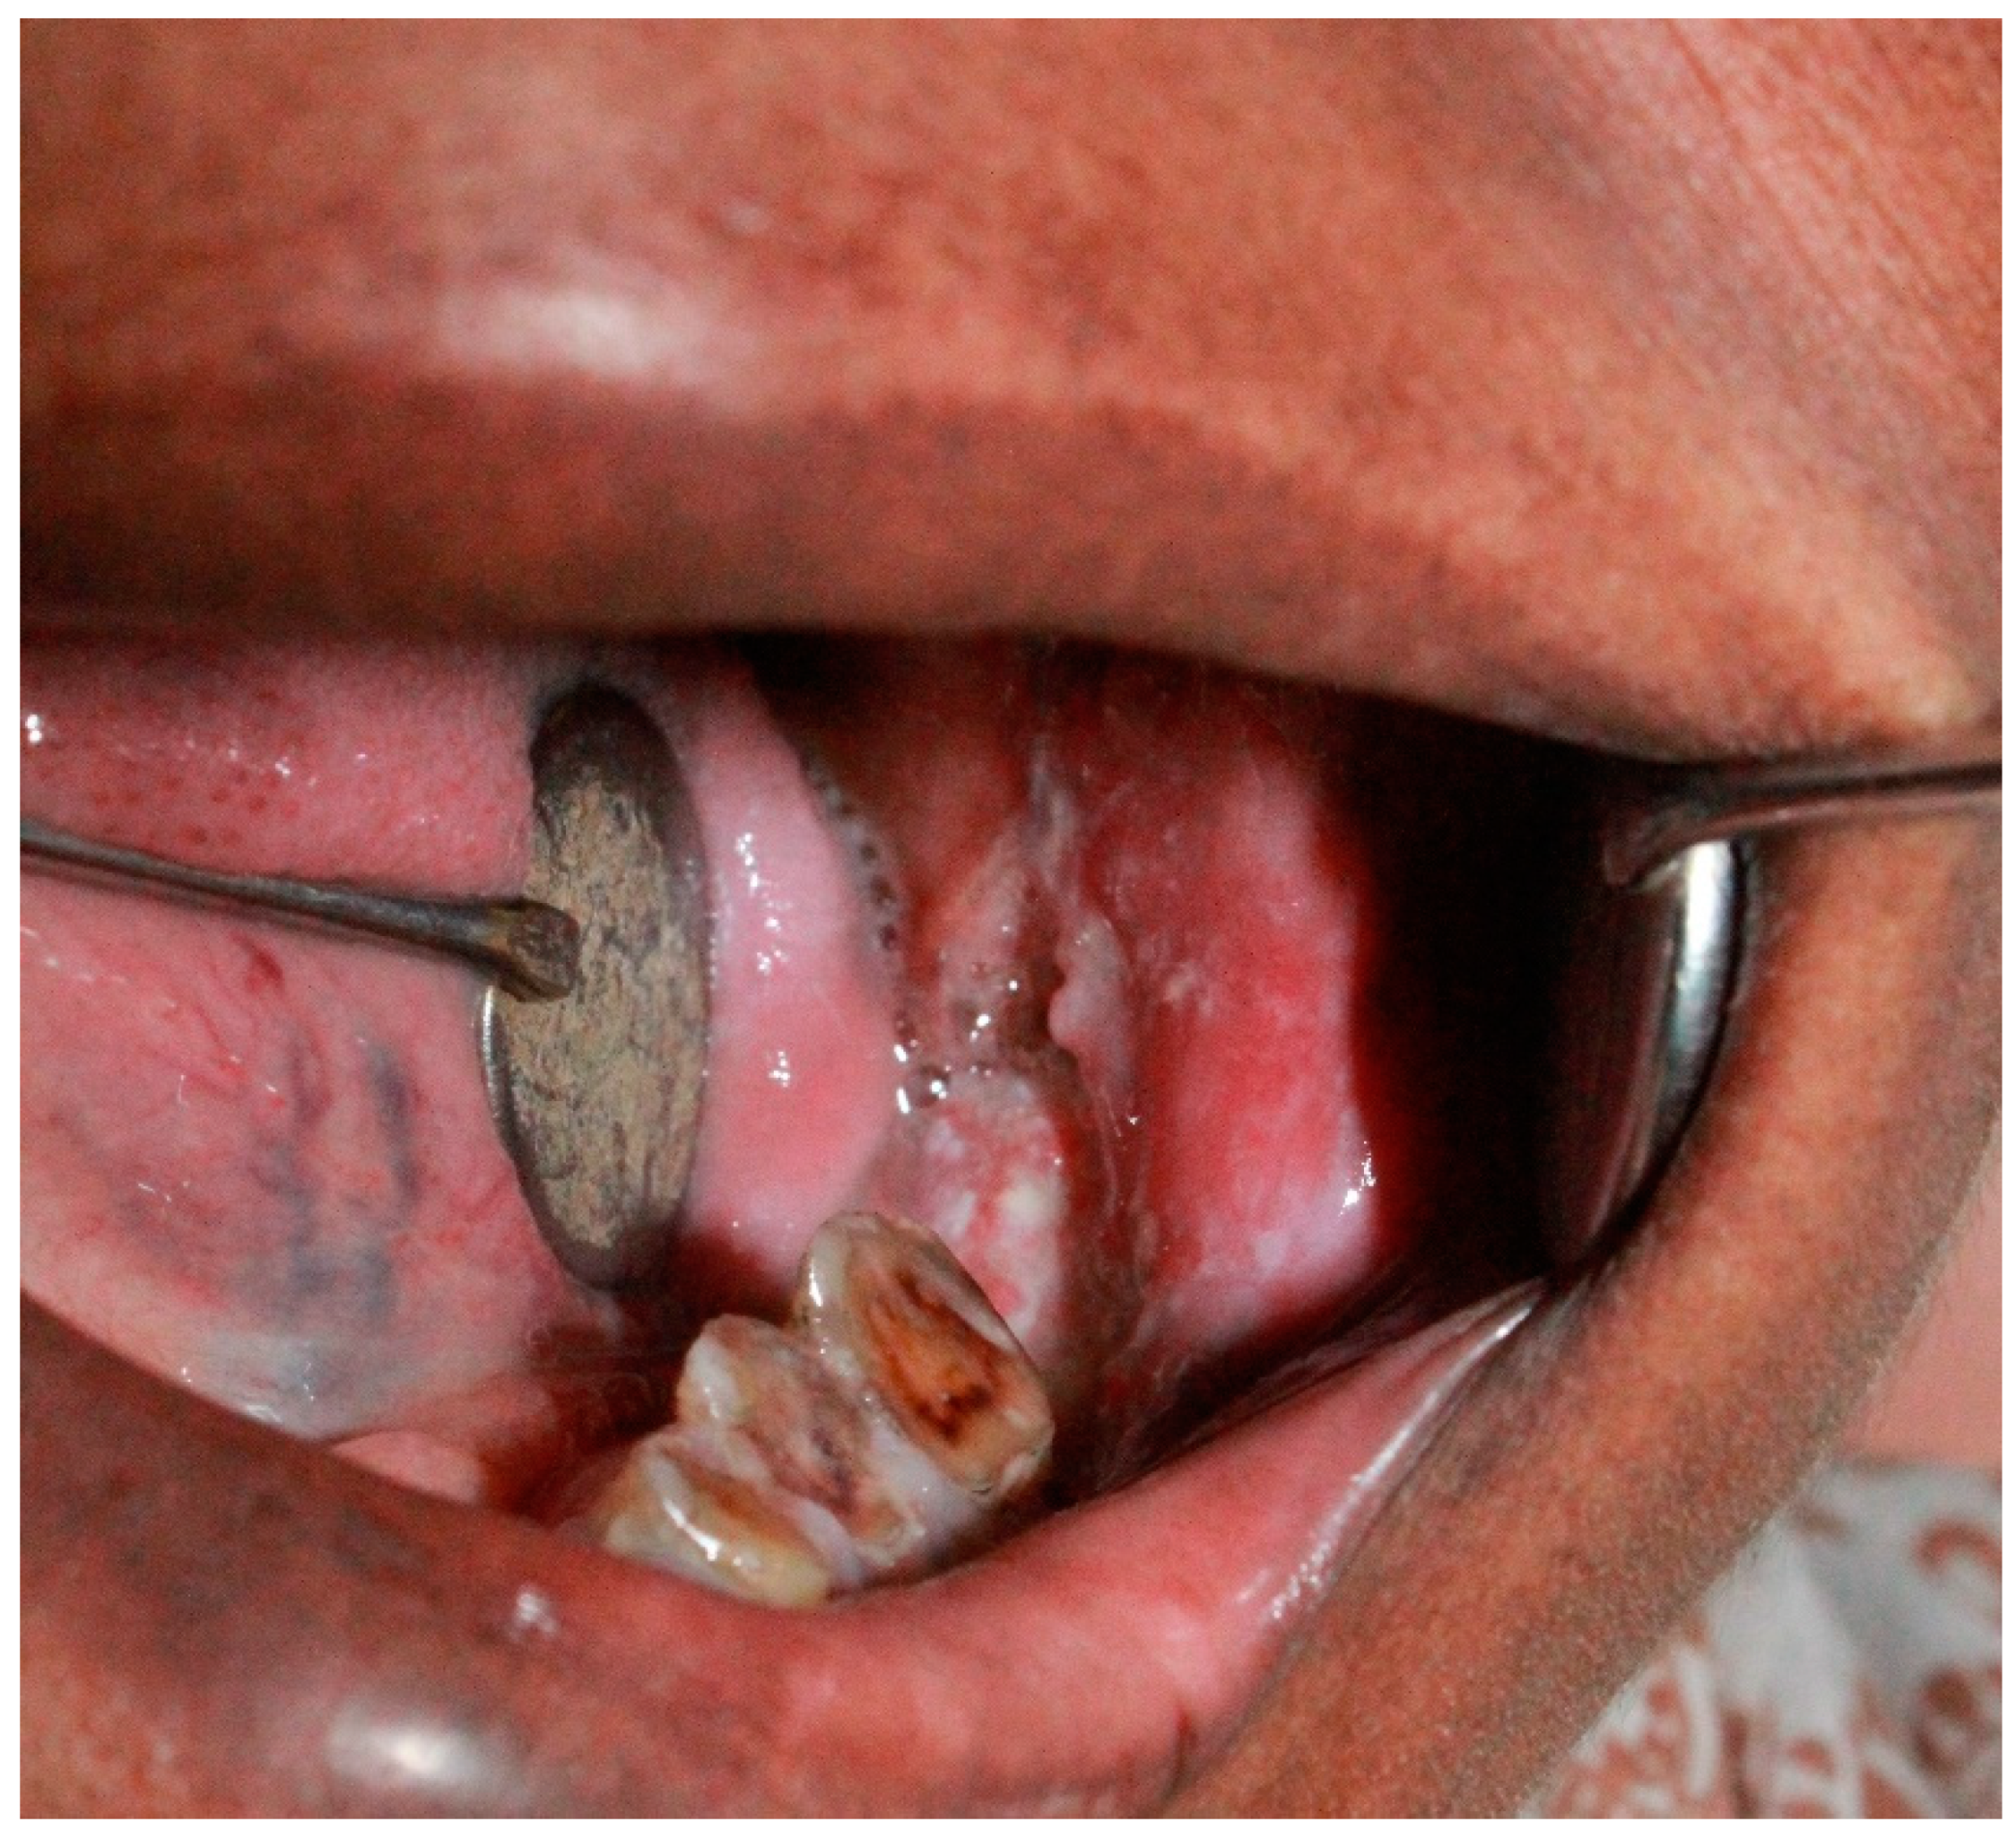

- Patients showing signs and symptoms of candidiasis, such as dysphagia, poor oral hygiene, dry mouth, altered taste sensation, halitosis, pain, whitish patch, and reddish patches.